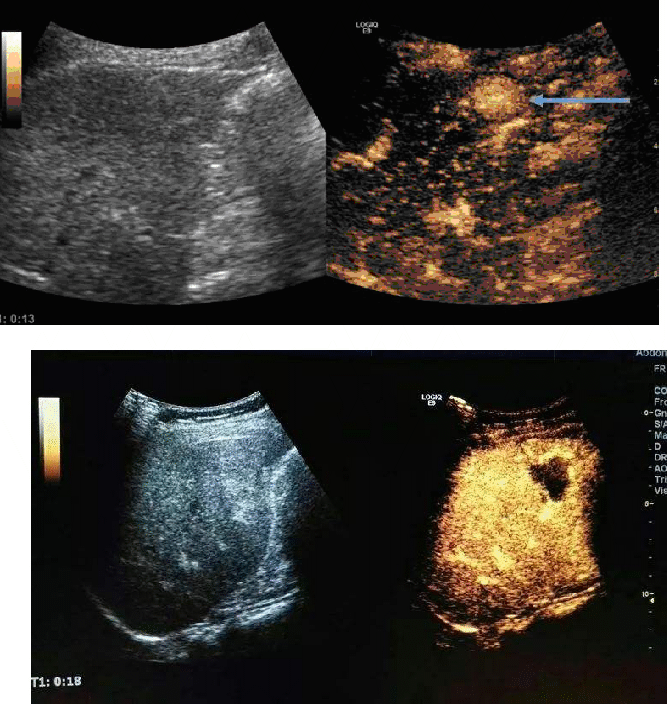

●超声造影

超声造影(Ultrasonic Contrast)又称声学造影(Acoustic Contrast),是利用造影剂气体微泡产生的强烈散射,达到有效增强肝、肾等实质器官内的微细血流或心血管内血流显示的目的,反映正常组织和病变组织在弥散或微循环水平的血流灌注情况,借此可以更加准确的判断病变的性质,提高诊断的分辨力、敏感性和特异性的技术。超声造影剂是血管血池性造影剂,不会进入组织间隙,不能通过血脑屏障,而且造影剂的惰性气体经呼吸排除体外,没有心肝肾毒性,不含碘剂,过敏反应相较于其他影像学造影剂低得多,具有高安全性、可重复性以及低副作用等优点。目前超声造影广泛应用于临床肝脏、肾脏、甲状腺、乳腺等脏器检查,在肿瘤的检出和定性诊断中有着重要意义,尤其是在肝脏肿瘤(检测1cm以下的亚厘米病灶方面)诊断方面,声学造影具有明显优势。